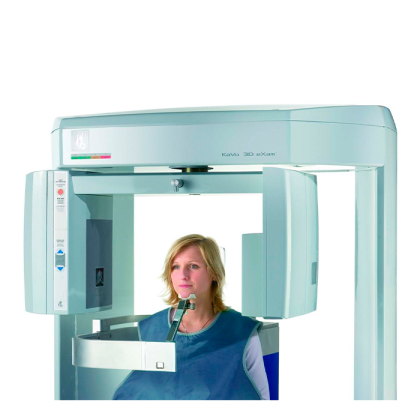

Компактные габариты устройства позволяют интегрировать его в стандартные стоматологические кабинеты, а простота управления делает его доступным даже для менее опытных пользователей. Пациент во время съемки размещается на специальном кресле, что минимизирует движение и гарантирует высокое качество изображений.